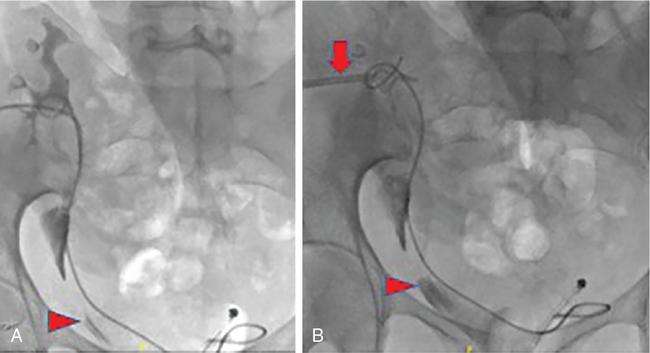

NONVASCULAR RENAL INTERVENTION Amitha Vikrama Nonvascular renal interventions have come a long way and have significantly reduced the surgical mortality and morbidity. It also paves way for short hospital stay and thus reducing the chances of nosocomial infection. They are usually pinhole or keyhole procedures with less distortion of the anatomy and physiology. They vary from image-guided aspiration/biopsy to percutaneous nephrostomy to complex procedures like ureteric stenting, strictureplasty, percutaneous nephrolithotomy etc. Iversen and Brun were the first to perform percutaneous renal biopsy of native kidneys in 1951. Over the years, newer imaging and biopsy techniques have evolved which have increased the biopsy yield to >95% and significantly reduced the complications of renal biopsy, resulting in decreased mortality rates from 0.12% to 0.02% during the last 50 years NOTE: Solitary renal mass lesions suspicious for malignancy should not be subjected to percutaneous biopsy, as there are chances of tumour seeding along the biopsy track. Excision biopsy is preferred for those lesions as it can be curative. USG-guided renal biopsy is the preferred method over blind biopsies. It avoids nontarget biopsies and reduces bleeding risks. Usually the lower pole of the kidneys is preferred site in native renal biopsy. The needle has to be directed into the lower cortex and care taken to avoid renal medulla and collecting system. 18G trucut biopsy needles are usually used in adults. In paediatric population, 20G can be used. Rarely, Coaxial technique is used in very obese patients and in those who are unable to lie prone. It is usually done as an inpatient procedure. Four hours of fasting is required to prevent aspiration of gastric contents during the procedure. Antiplatelets and anticoagulants are stopped at least 3–5 days prior. Informed written consent has to be taken after explaining the risks and benefits of the procedure. Patient is to be positioned in prone and USG-guided marking of the site of biopsy done prior to cleaning and draping. The depth of the renal cortex from the skin surface has to be noted. If the ribs are coming in line with the lower pole cortex, then a cranially angulated path is preferred. After infiltration of 2% lignocaine, the biopsy needle is advanced up to and not into the lower pole cortex. As the kidney keeps moving with respiration, the biopsy should be properly timed to avoid hitting the collecting system and medulla. This method is real-time ultrasound guided renal biopsy (Fig. 10.21.1.1). There is another method practiced in few of the institutes where the location of lower pole of the kidney is marked on the skin after ultrasound screening. The marking corresponds to the lower most renal cortex at the end of normal inspiration and the biopsy path will be perpendicular to the bed without any craniocaudal or mediolateral angulation. The distance between the skin and the renal cortex is measured. The patient will be instructed strictly not to change his position. Then the biopsy will be done blindly without any real time USG guidance. With this method, more number of patients can be biopsied in a short interval time. In a transplanted kidney, which is usually grafted in the iliac fossa, biopsy can be obtained from upper or lower pole. Points to remember: Cortical tangential and cortical non tangential approaches have been described (Fig. 10.21.1.2). Cortical tangential approach is described to have better diagnostic yield with lesser complications. In this approach, the needle track will be almost parallel to the capsule so that only the cortical tissue is targeted (Fig. 10.21.1.3A–C). Renal biopsy can also be done with coaxial technique. In this method, a coaxial needle, one size bigger than the biopsy needle, usually 17G, is inserted up to the renal capsule. The stylet is then removed and the 18G biopsy needle is inserted through the coaxial needle and the required number of biopsy specimens obtained. After this, the rent in the capsule can be sealed off with gelatine plugs before removing the coaxial needle. This helps in preventing bleeding complications. In patients with high risk of bleeding due to coagulation abnormalities, transjugular renal biopsy can be done in which renal vein is cannulated and biopsy done from within (Fig. 10.21.1.3D–F). In obese patients who cannot lie prone, biopsies are done in lateral or oblique lateral positions under CT or USG guidance. CT guidance is especially helpful when the visualization of the kidney is difficult on ultrasound. In these cases, coaxial technique is always helpful. In 2019, KHA-CARI guidelines were first published for renal biopsy. A few of the salient recommendations are given below: It is an image-guided procedure in which the renal pelvicalyceal system is accessed percutaneously which is predominantly used for decompressing an obstructed system and also for various other therapeutic procedures. It is usually done under local anaesthesia and IV sedation. Major procedures might require general anaesthesia. All routine preprocedural blood tests and coagulation profile should be done. Appropriate antibiotics are administered intravenously prior to the procedure. 21G needle, 018 and 035 wires, appropriate dilators, sheath and pigtail drainage catheter. Ultrasound and fluoroscopy is required for guidance. Patient is usually positioned prone on the table. Under special circumstances, lateral or oblique positions are also used. After instillation of local anaesthesia, a 21G needle is used to access the renal calyx under USG guidance. Once the urine flow is seen, nonionic contrast is injected to delineate the renal collecting system. A 018 wire is passed through the needle into the pelvicalyceal system and later exchanged for a 035 wire. Appropriate tissue dilators are used to dilate the track before placing a pigtail drainage catheter. The drain is secured by stay sutures and connected to a urobag. The initial urine sample is to be sent for culture and sensitivity (Figs. 10.21.1.4–10.21.1.6). Ureteric stenting was first described by Zimskind et al endotracheal tube al in 1967. It is one of the commonest procedure done in urology practice It is usually done after doing a percutaneous nephrostomy. The percutaneous nephrostomy (PCN) drain is replaced with a 6F or 8F sheath over a guidewire and ureterogram is obtained to assess the site of stricture or obstruction. Using a catheter and guide wire combination, the stricture is negotiated and the exchange length hydrophilic wire is parked in the bladder. The ureteric length is measured and appropriate-sized double J (DJ) stent is inserted over the wire. Care is taken to get the loops formed at both ends of the DJ stent so that stent migration is prevented (Fig. 10.21.1.7). A variety of delivery systems are available for the deployment of the ureteric stent exist: pusher mechanism, string release and sheath (similar to an inferior vena cava (IVC) filter). Post stent insertion, the nephrostomy drain can be retained for a couple of days. The drain is closed externally and USG screening is done the next day to confirm antegrade flow after which the drain can be removed.